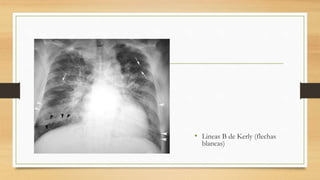

• Son confiables los signos

radiográficos de edema vascular e

intersticial (Lineas B de Kerly)

• Lineas B de Kerly (flechas

blancas)